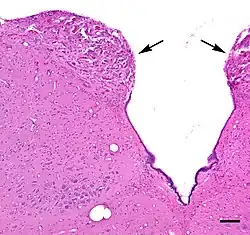

Micrograph of the area postrema (arrows) in a transverse section through the lower brainstem of a squirrel monkey (Saimiri sciureus). Hematoxylin and eosin stain; Bar=100 microns (0.1 millimeter).